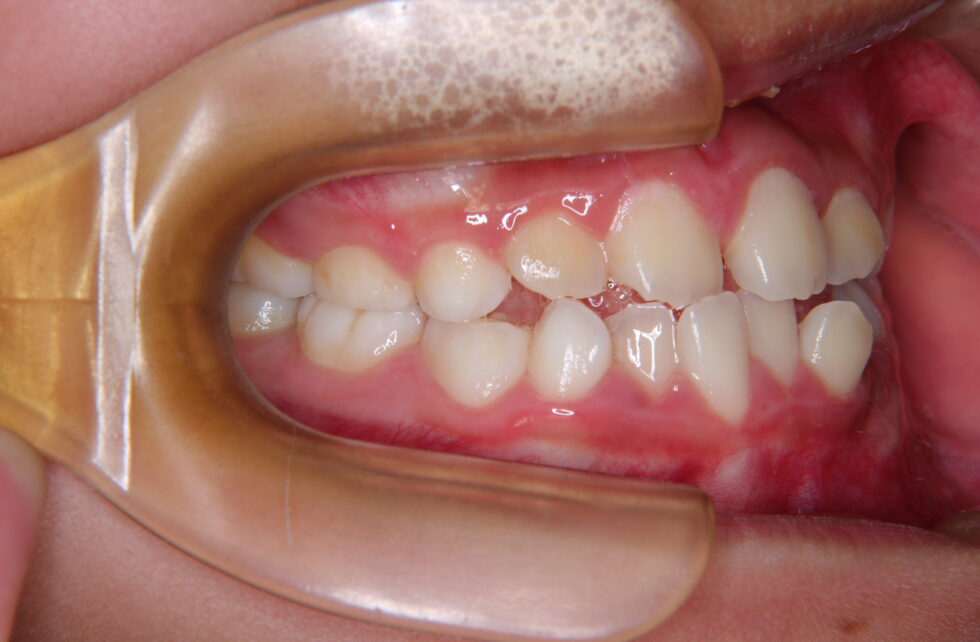

初診時年齢9歳の女性。叢生を伴う反対咬合のケース。

前歯部の反対咬合を主訴に来院されました。検査結果から骨格性の反対咬合であったため、上顎前方牽引装置を10ヶ月間使用して反対咬合の改善を行い、永久歯への生え変わりが完了した後にマルチブラケット装置を使用して非抜歯にて動的治療を行いました。反対咬合の改善とともに、乱れて生えていた永久歯も歯を抜かずに治療することが出来ました。

永久歯列での動的治療期間は1年11ヶ月間